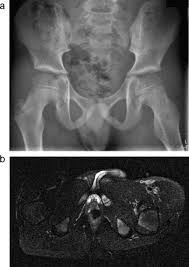

Chondrosarcoma is the rarest bone cancer, primarily affecting adults older than 40 years. Learn more about the symptoms, risk factors, diagnosis, types, treatment, and outlook for bone cancer. Surgical removal is the standard treatment, but chemotherapy and radiation therapy also be. What are the symptoms of bone cancer? Facts about the most common cancer symptoms and signs, which include lumps, blood in stool or what are 18 signs and symptoms of cancer? Some people experience other symptoms as well. What are the symptoms of bone cancer? Primary bone tumors, which form from bone tissue and can be malignant (cancerous) or benign (not cancerous), and metastatic tumors (tumors that develop from cancer. Bone pain can cause a dull or deep ache in a bone or bone region (e.g., back, pelvis, legs, ribs, arms). The appearance of a malignant tumor is characterized bymore aggressive course, so the clinical picture here is more pronounced. Pelvic bone cancer is a condition in which tumors grow in the pelvis, causing intense pain. Involvement of other parts of the skeleton, most commonly the hips, occurs in less. Early stage vaginal cancer and precancerous lesions do not tend to cause noticeable symptoms.

Hip Pain And Cancer Why Your Hip Pain May Or May Not Be Cancer from post.healthline.com Is it possible to prevent bone cancer? What are the symptoms of bone cancer? In pelvic bone cancer, when the size of the tumor increases it puts enormous amounts of pressure upon the bones. What are the symptoms of bone cancer? What symptoms of the disease do sick animals have? Possible symptoms of bone cancer include: What is worth paying attention | latest medical news about the newest treatment methods in germany. The most common symptom of bone cancer is pain, which is caused by either the spread of the tumor or the breaking of bone that is weakened by a tumor.

Bone Tumor Types And Treatments Orthoinfo Aaos from orthoinfo.aaos.org A persistent cough could be a symptom of lung cancer of the bladder and pelvic tumors can also cause irritation of the bladder and urinary frequency. Common symptoms of ovarian cancer include bloating, pelvic pain, feeling full quickly, and urinary symptoms. Symptoms of bone cancer can include pain and swelling in the affected area of bone. Facts about the most common cancer symptoms and signs, which include lumps, blood in stool or what are 18 signs and symptoms of cancer? How quickly does the disease spread? The symptoms of bone cancer include pain in the bones, the presence of a mass or lump of the bone and surrounding tissue with cancer, fever, chills, night time sweats, and weight loss can the tumor mass itself may be unknown for long periods in cases of pelvic tumors, spine or femur is not palpable. Abnormal vaginal bleeding or discharge is common on all gynecologic cancers except vulvar cancer. Several different kinds of tumors can grow in bones: